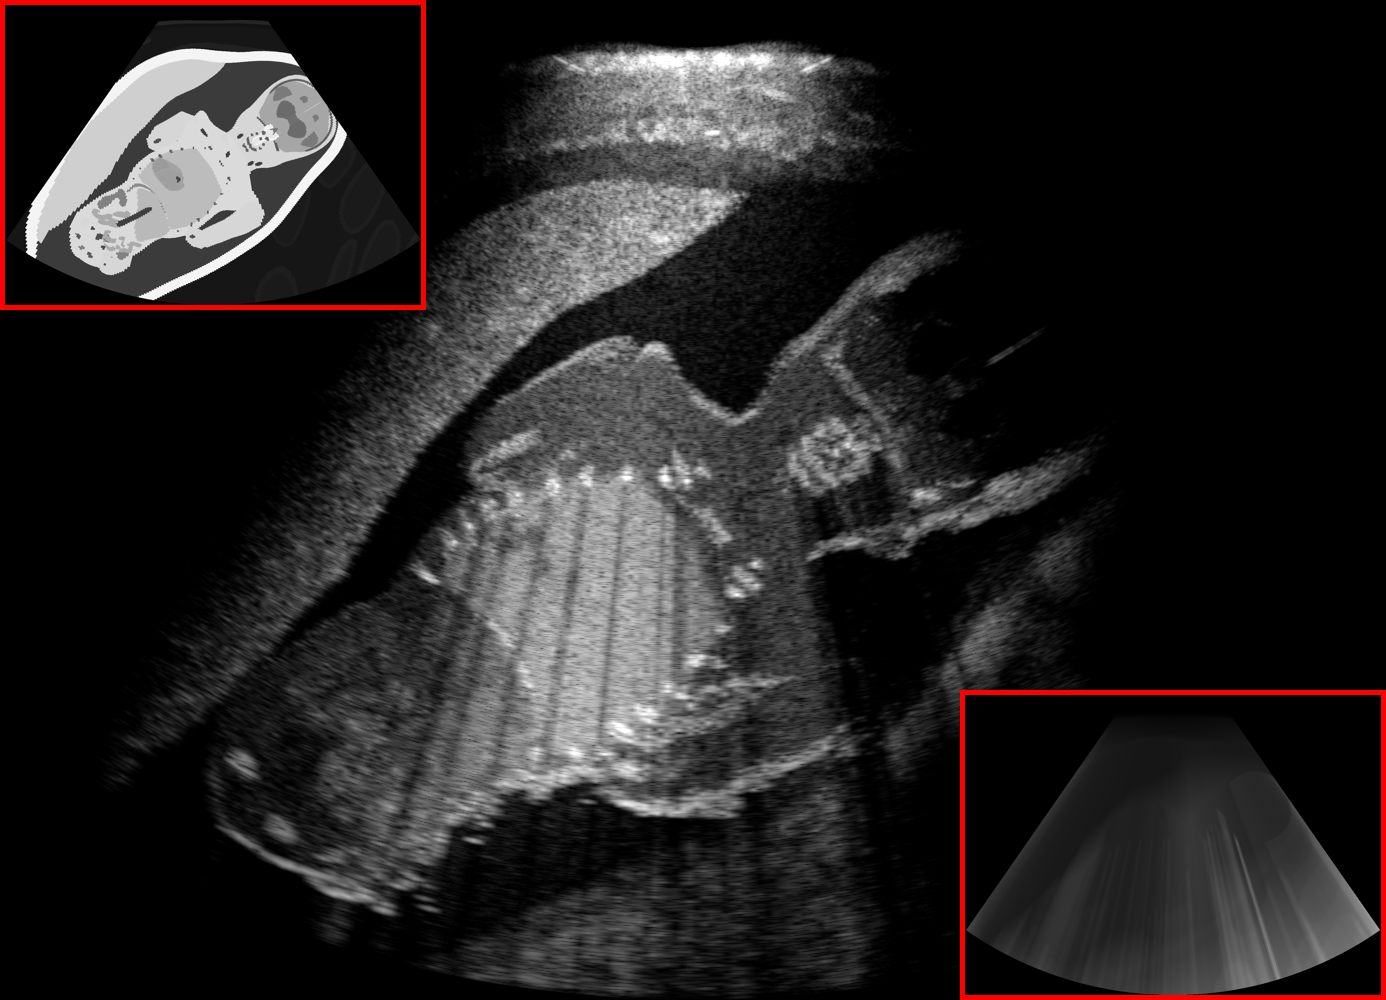

In this work, we propose to learn the rendering of ultrasound images given only cross-sectional model slice / segmentation and integral attenuation maps, the latter of which can be derived from former on-the-fly and helps distill global acoustic energy information locally. An overview of per-frame segmentation and integral attenuation map generation can be seen in Fig. 1(a).

In contrast to [18], herein we propose the following four major architectural improvements, as also illustrated in Fig. 1, which are later demonstrated to provide promising generation results in our experiments.

Input to all channels: To enable an effective information flow from the input images to each spatial resolution in the network, we provide the information at each intermediate layer by concatenating the maps along the channel dimension to the network activations, indicated by dotted blue connections in Fig. 1(c). Although this was shown in [20] to be inferior to spatially-adaptive normalization (SPADE) layers in the context of natural images, we found this approach to outperform SPADE in our application setting, since it enables the network to generate location-specific features conditioned on both segmentation and integral attenuation map. In our ablation experiments, we refer to this concatenation approach with the acronym concat.

Preserving spatial information: To further preserve the local information from input maps to output images, we use a comparatively small receptive field in our network architecture. Since the integral attenuation map helps to transform global effects of acoustic shadows into local features, understanding and encoding the entire scene in a compact form is not required and would waste network capacity. We therefore use 4 downsampling blocks.

Texture-friendly decoder: Transposed convolutions are known to be prone to characteristic checkerboard artifacts due to uneven overlap when using odd kernel sizes [21]. Therefore they are not an ideal choice in texture generation tasks. To improve texture generation performance, we therefore enhance the decoding blocks by introducing additional stride-1 convolution layers, which helps to circumvent both low and high frequency artifacts. These changes in the convolutional architecture are referred collectively using the acronym conv in our ablation study.

Stochastic texture generation: To generate random speckle textures, the network needs access to a stochastic source, especially when omitting low-quality B-mode image input. A straightforward approach to ensure a stochastic process is to feed an explicit noise image as an additional input channel. Recently, Karras et al. [22] proposed an alternative method, by perturbing feature channels using additive Gaussian noise with learned per-channel weighting. This warrants the network to disentangle global and local stochastic variations. Motivated by its astonishing performance in generating fine stochastic details such as hair, we study this approach for the generation of ultrasound textures. Accordingly, Gaussian noise images with different sizes are generated and weighted by a learned per-channel scaling factor. The weighted noise channels are then added to the decoding feature layers after skip connections, shown as solid red lines in Fig. 1(c). In the ablation study we referred to this technique with the acronym noise. The more conventional way of adding noise as an input layer is equivalent to replacing the low-quality image in [18] with noise, and therefore is referred as NSA2H in our comparative study.